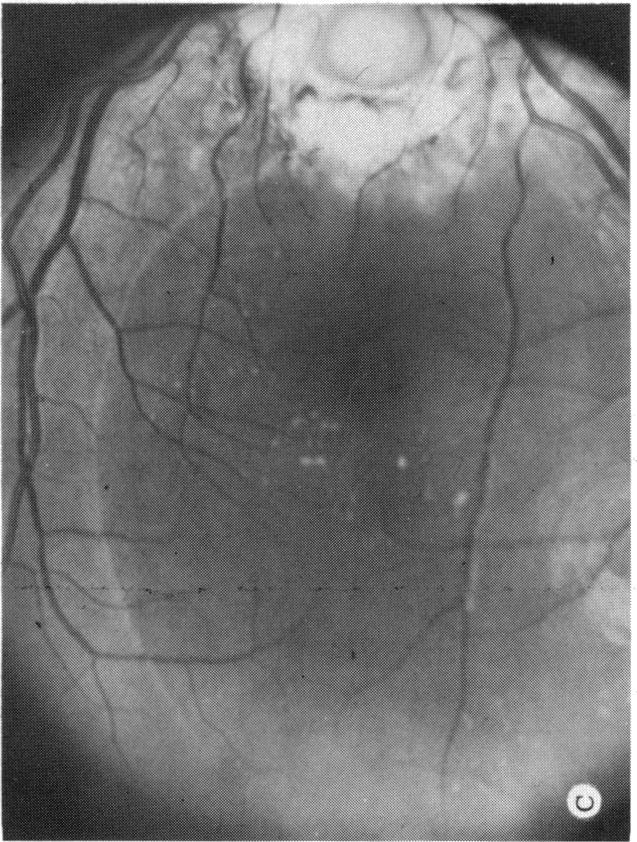

Six cases of congenital pit of the optic nervehead associated with posterior serous retinal detachment are presented. All were treated by photocoagulation along the disc margin in the area of retinal detachment. In five cases reattachment of the retina occurred, after the clinical development of a film chorioretinal adhesion at the disc margin, and appeared to be secondary to the treatment. The sixth case (Case 4), although treated, appeared to represent a spontaneous reattachment. This disorder, which frequently results in permanent decrease of central vision, affected the better, or only, eye in two of the six cases herein reported. Fluid, probably from the vitreous cavity, appears to gain access to the subretinal space via the pit. Reattachment in treated cases occurred only if an effective chorioretinal adhesion was created over the entire area of the fistulous detachment at the disc margin. Field defects after treatment appear to be secondary to either the optic pit itself or the longstanding retinal detachment, oftern accompanied by pigmentary degeneration and cystic macular degeneration, rather than juxtapapillary photocoagulation treatment.

本文报告6例先天性视神经乳头凹合并浆液性视网膜脱离。所有病例均采用视网膜脱离区域沿视盘边缘光凝治疗。5例视网膜脱离在视盘边缘形成脉络膜视网膜粘连后复位,似乎是治疗的继发结果。第6例(病例4)虽经治疗,但似乎是自发复位。这种疾病常导致中心视力永久性下降,在本文报告的6例中有2例影响了较好或仅有的一只眼。液体可能来自玻璃体腔,似乎通过视神经乳头凹进入视网膜下间隙。治疗病例中,只有在视盘边缘瘘管性脱离的整个区域形成有效的脉络膜视网膜粘连时,视网膜才会复位。治疗后的视野缺损似乎继发于视神经乳头凹本身或长期视网膜脱离,常伴有色素性变性和黄斑囊样变性,而非视盘旁光凝治疗。